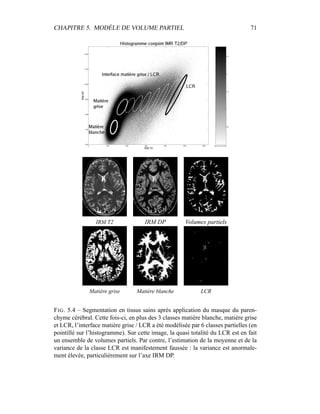

Si ces substituts peuvent être considérés comme des biomarqueurs, très peu de

biomarqueurs atteignent le stade de substitut de marqueur clinique : la plupart des

CHAPITRE 9. ANNEXES 171

quantificateurs issus de l’imagerie sont donc “évalués” (évaluation du facteur de

risque) plutôt que “validés” (preuve du pouvoir prédictif). Typiquement, l’éva-

luation de ces biomarqueurs issus de l’imagerie comprend un certain nombre de

points comme la reproductibilité des résultats, une forme d’invariance à un chan-

gement d’échelle (changement d’appareil d’acquisition, étude multi-centre, etc.),

la comparaison avec des données plus fiables (histopathologie, par exemple) et